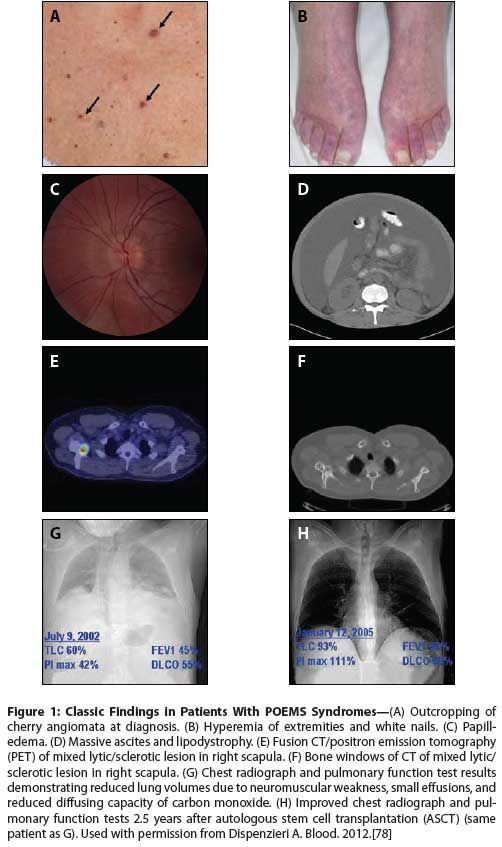

Skin manifestations include hyperpigmentation, a recent outcropping of hemangiomas, hypertrichosis, dependent rubor and acrocyanosis, white nails, sclerodermoid changes, flushing, or nail clubbing (Figures 1A, 1B).[7,9,11,15-19] Nail clubbing is seen in ~4% of cases, but some studies have reported rates as high as 49%.[8,20]

Papilledema is present in at least one-third of patients (Figure 1C). Of the 33 patients at our institution who underwent at least one formal ophthalmologic examination during a 10-year period, about two-thirds (67%) had ocular signs and symptoms, the most common of which was papilledema, seen in 52% of those examined.[21]

Extravascular overload most commonly manifests as peripheral edema, but pleural effusion, ascites, and pericardial effusions are also common (Figure 1D). The ascites can be so severe that weekly paracentesis is required. The composition of the ascites was studied in 42 patients with POEMS syndrome. The ascitic fluid had low serum-ascites albumin gradients, consistent with an exudative process rather than a portal hypertension process in 74% of cases.[22]

Osteosclerotic lesions occur in approximately 95% of patients, and can be confused with benign bone islands, aneurysmal bone cysts, non-ossifying fibromas, and fibrous dysplasia.[8,10,40,41] Some lesions are densely sclerotic, whereas others are lytic with a sclerotic rim, and still others have a mixed soap-bubble appearance. Bone windows of CT body images are often very informative, often even more so than [F-18]fluorodeoxyglucose (FDG)-uptake by positron emission tomography (PET), which can be variable. Underlying these lesions are clonal plasma cells (Figures 1E, 1F).

The pulmonary manifestations are protean, including pulmonary hypertension, restrictive lung disease, impaired neuromuscular respiratory function, and impaired diffusion capacity of carbon monoxide, but many of these symptoms improve with effective therapy (Figures 1G, 1H). No direct association has been documented between the digital clubbing seen in POEMS syndrome and lung disease.